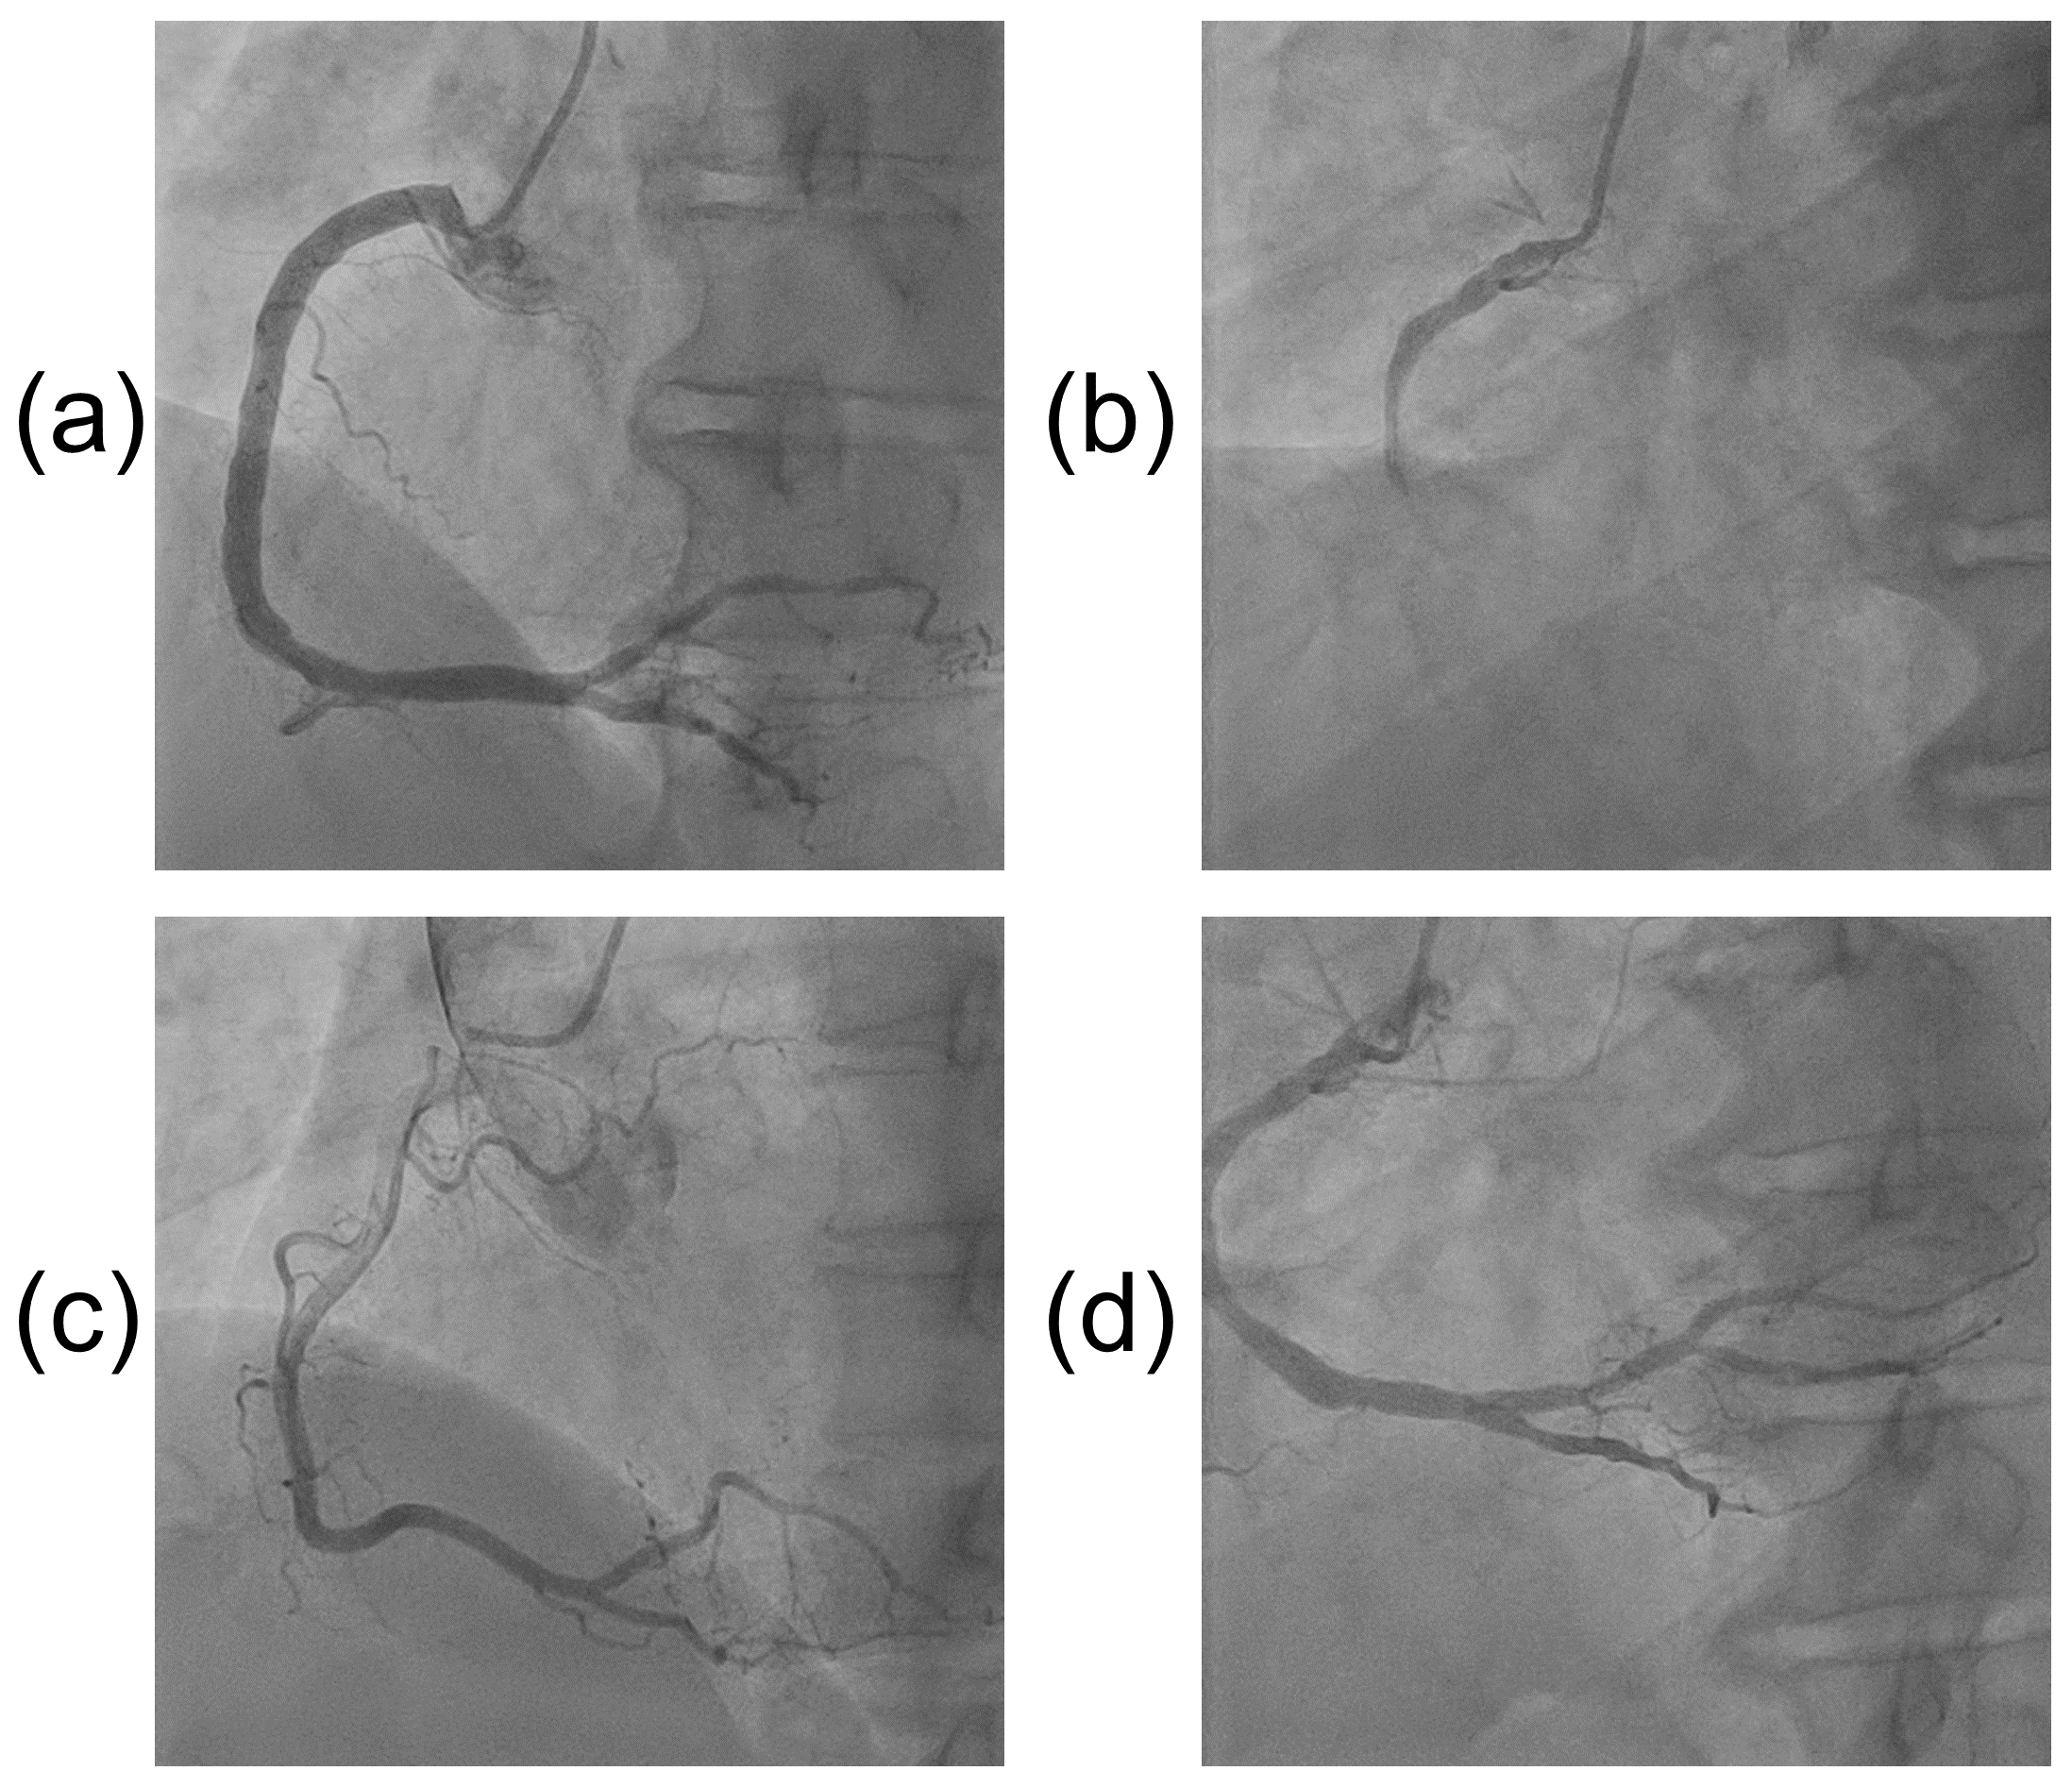

Refer to caption

Figure 2: Side-by-side comparisons between LAO and RAO angiograms. Each LAO-RAO pair represents one patient.

Our three-stage pipeline is trained on data from one specific angular projection of a set of up to 9 projections in cardiology practice, namely the LAO straight projection of the right coronary artery. The Right Anterior Oblique (RAO) projection of the RCA is taken at approximately right angles to the LAO, such that the vessel is the same but has a slightly different shape and appearance due to the orthogonal view projection. Fig. 2 shows examples of side-by-side comparisons between the two views. Given the similarities in vessel anatomy, we tested the ability of our trained classification and segmentation models that had only previously seen LAO data to also interpret RAO data. Through this extension, we examined our algorithms’ capability to generalize on unseen but related data. We used a test set of 17 RAO videos with 1500 frames (1038 non-key and 462 key). Subsequent results are generated using the test set. In the first two stages of key frame extraction and vessel segmentation, the RAO videos were processed using the trained LAO model weights. For the purpose of evaluating the generalizability of our model, no additional model training on RAO data was done. In the third stage, the same stenosis measurement algorithm was used.